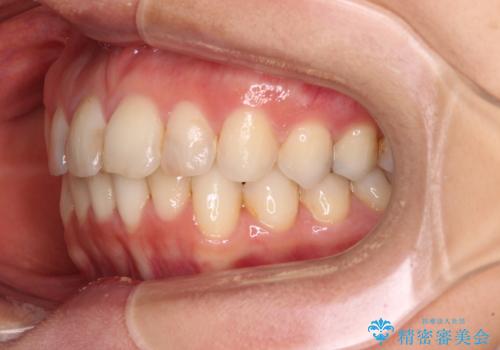

前歯の叢生をいつの間にか改善 インビザラインによる矯正治療

- 前歯のデコボコを気にして来院された患者様です。

IPR(歯と歯の間を削る)によってデコボコが解消するように設計し、インビザラインにより治療を行うこととしました。

下顎善の叢生をもう少し改善したかったのですが、患者様は十分に整ったとのことで治療を終えることになりました。